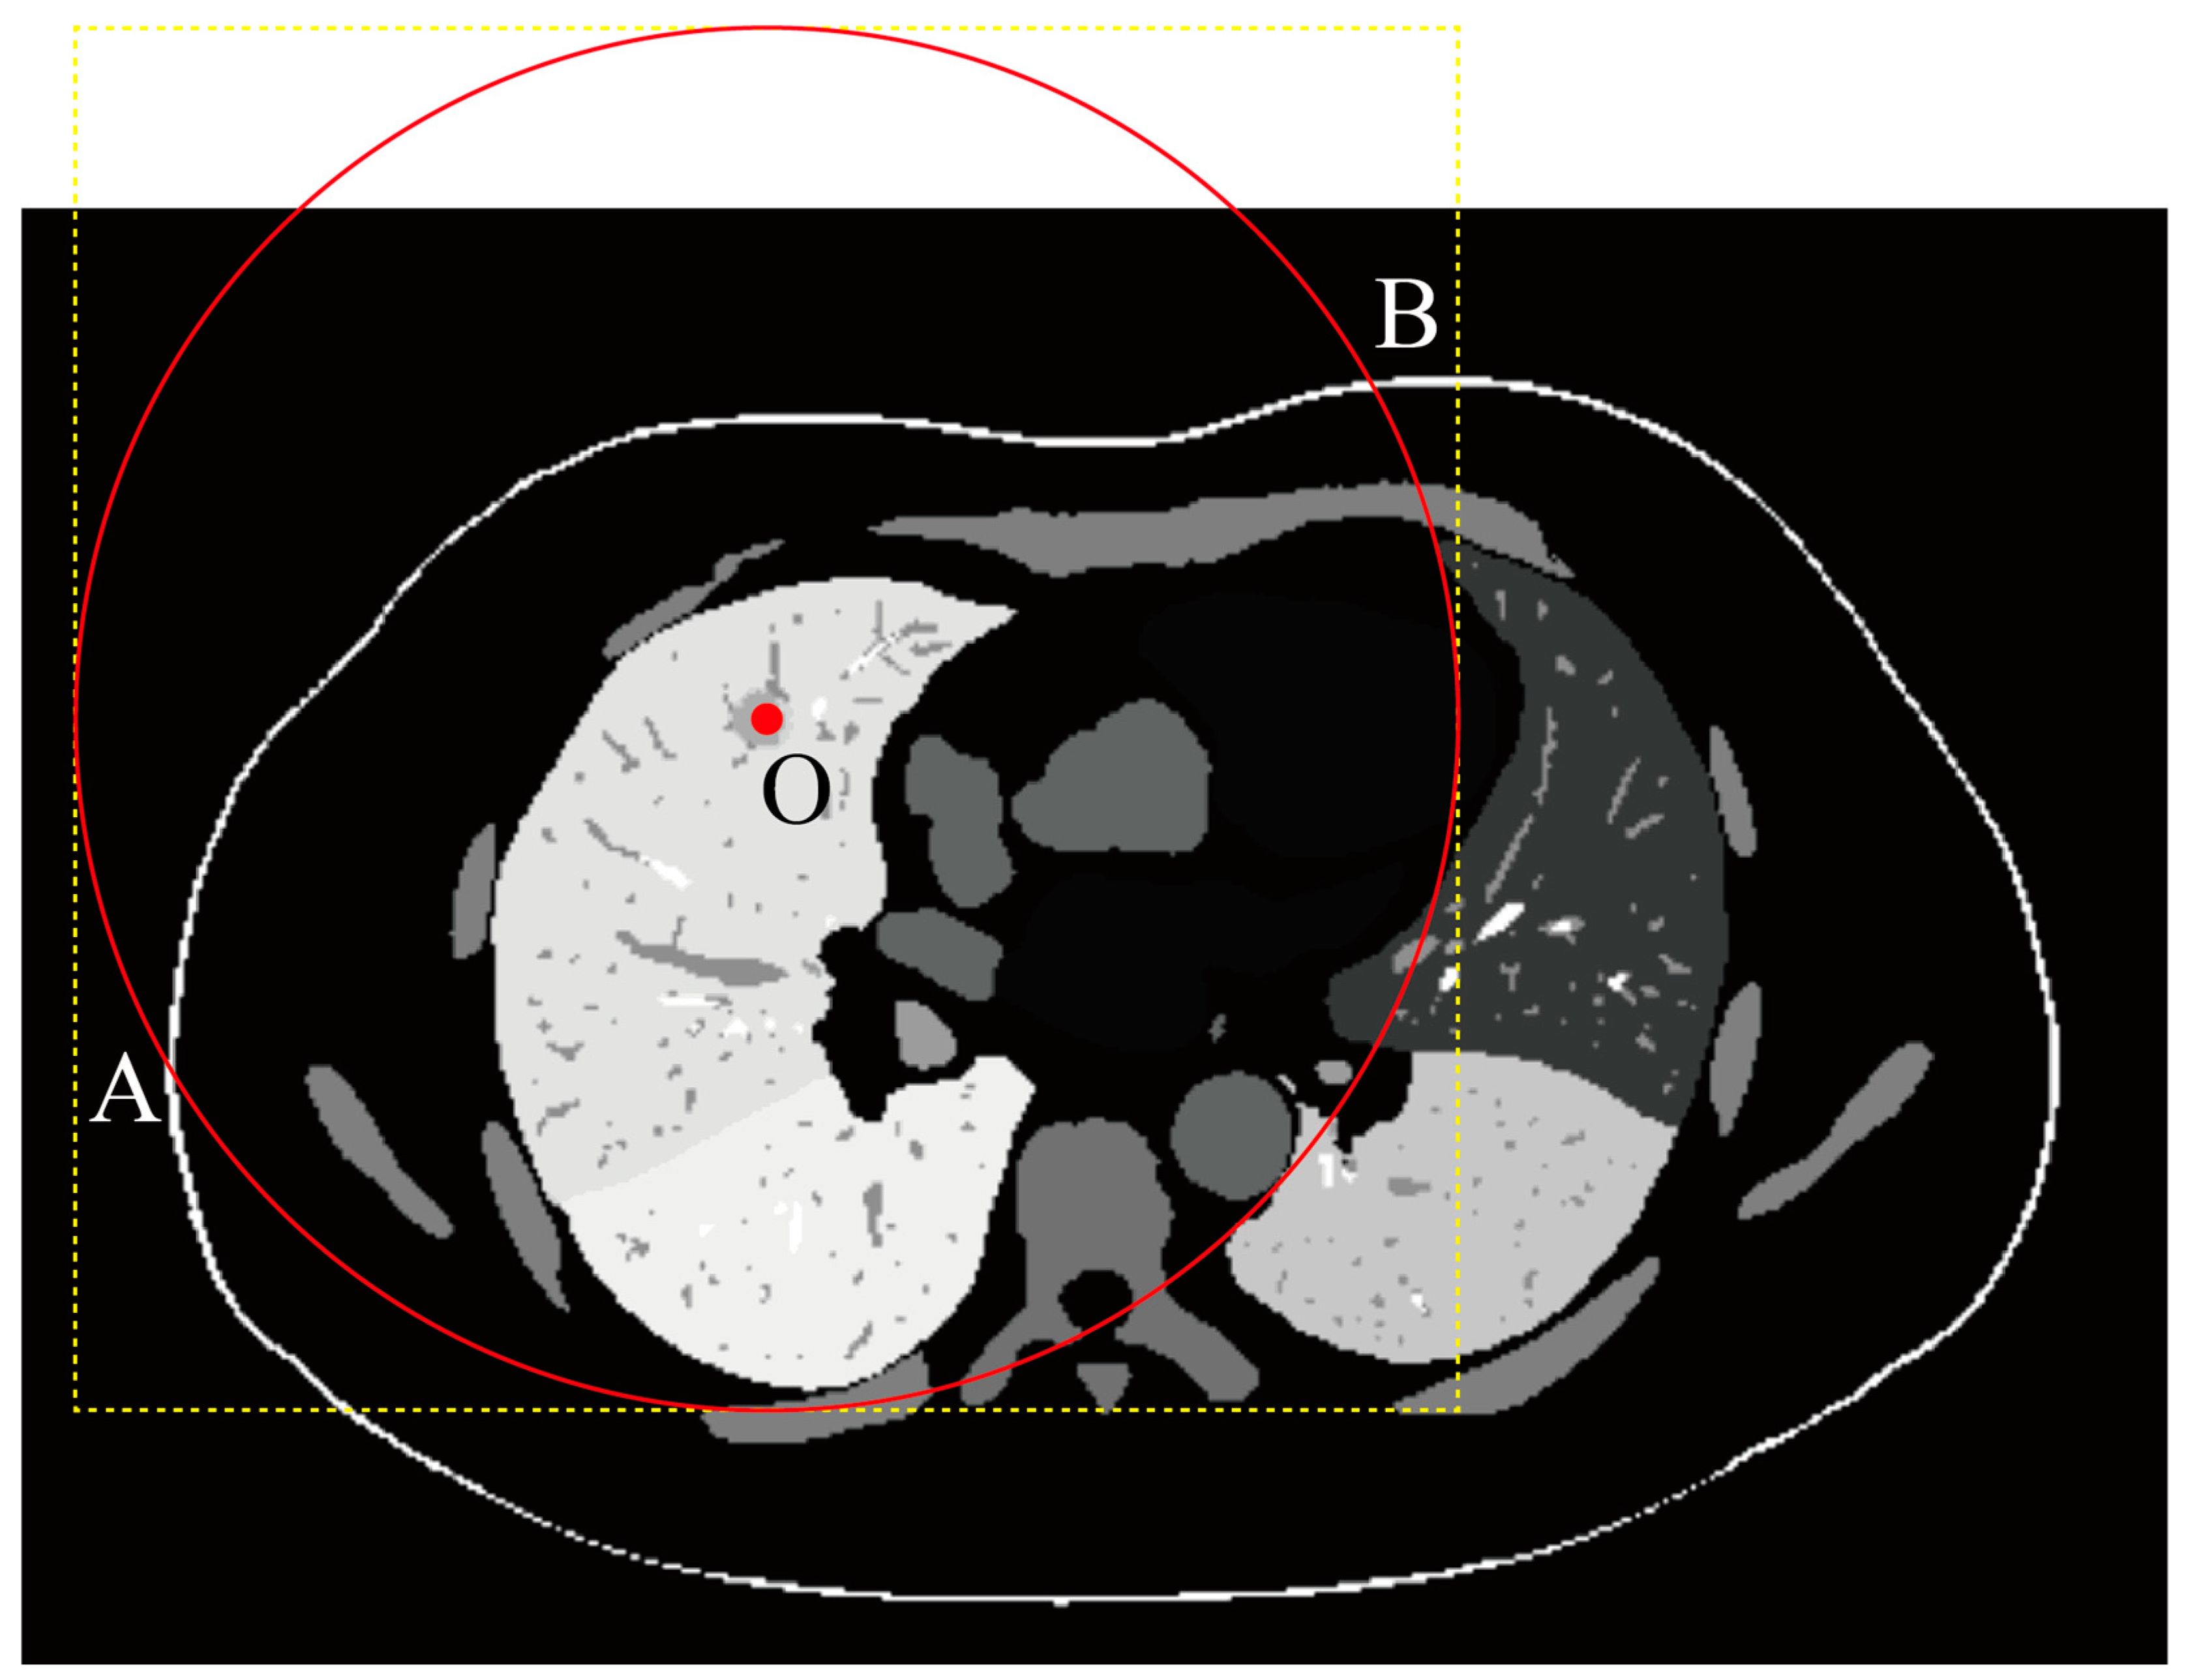

Following mask resampling, we proceed with ROI cropping to extract the pertinent area from the larger image volume. This step reduces data size, minimizes computational load, and eliminates irrelevant information. The cropping method involves drawing a sphere centered at the target point with a radius equal to the biopsy needle length and cropping along the bounding box of this sphere. To handle cases where the bounding box exceeds the CT image boundaries, we employ zero-padding. This padding does not introduce artificial data, and irrelevant regions are automatically excluded during computations. Additionally, we symmetrize the ROI to avoid asymmetrical calculations if the target is not at the center, thereby preventing issues related to varying distances and angle ranges. Figure 5 demonstrates the procedure described above.

Figure 5.

Workflow of the ROI extraction and zero-padding procedure. The red circle represents a sphere with a radius corresponding to the length of the biopsy needle (R). Points A and B mark the intersections of the red circle with the skin surface. The puncture target point O is first located, and an ROI boundary is defined by calculating with a radius equal to the biopsy needle length R. If the bounding box exceeds the image boundaries, zero-padding is applied to preserve symmetry. The yellow ROI is then cropped from the image. A spherical ROI with radius R is drawn, resulting in the red spherical ROI and shell. The region between the red spherical shell and the yellow bounding box is assigned a value of zero.